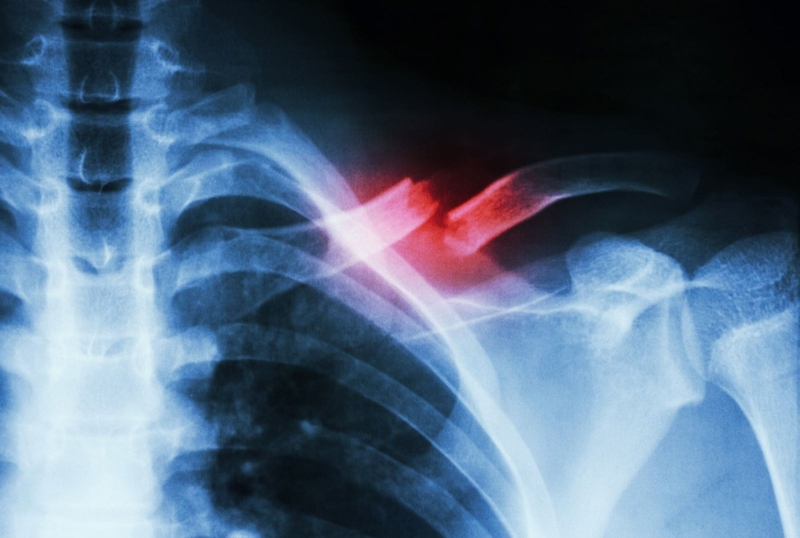

Bị gãy xương đòn bao lâu thì lành?

Bị gãy xương đòn bao lâu thì lành là câu hỏi được nhiều người quan tâm. Bởi trong cuộc sống sinh hoạt và lao động, xương đòn vai có thể bị gãy do nhiều nguyên nhân khác nhau. Tùy thuộc vào tình trạng xương bị tổn thương mà thời gian điều trị và hồi phục cũng sẽ khác nhau.

Theo thống kê, tỷ lệ người trưởng thành gặp phải tình trạng gãy xương vai chiếm 5% trên tổng các loại chấn thương trên cơ thể. Quá trình phục hồi nhanh hay chậm thường dựa vào mức độ tổn thương, cơ địa và sự tuân thủ phác đồ điều trị của người bệnh. Vậy bị gãy xương đòn bao lâu thì lành? Hãy tìm hiểu câu trả lời trong bài viết sau.

Gãy xương đòn vai (xương quai xanh) là chấn thương xảy ra phổ biến ở vùng vai. Theo thống kế, tỷ lệ gãy xương quai xanh chiếm khoảng 35 - 43% trên tổng trường hợp gãy xương ở vùng vai và khoảng 4% trên tổng trường hợp gãy xương cả cơ thể. Nguyên nhân dẫn đến tình trạng này thường do té ngã, tai nạn giao thông, tai nạn thể thao… Trong đó, tình trạng gãy xương quai xanh trái sẽ thường gặp hơn với gãy xương quai xanh phải. Nguyên nhân là do số người thuận bên phải nhiều hơn, bên tay không thuận có xu hướng yếu hơn nên sẽ dễ bị gãy hơn.

Xương đòn vai có thể gãy ở nhiều vị trí khác nhau trong đó gãy tại vị trí 1/3 giữa là điển hình nhất. Gãy xương đòn vai có 2 loại, đó là: Gãy đơn thuần và gãy ảnh hưởng đến hệ thần kinh, mao mạch như tổn thương màng phổi, tổn thương mạch máu, tổn thương thần kinh...

Bị gãy xương đòn bao lâu thì lành 1 Gãy xương đòn vai là chấn thương xảy ra phổ biến ở vùng vai

Xương quai xanh bị gãy thường rất dễ lành do xương quai xanh có màn xương rất dày và nằm ở vị trí phía trên lồng ngực được cung cấp máu dồi dào. Tuy nhiên, trong một vài trường hợp tình trạng gãy phức tạp, mảnh xương có thể đâm xuyên vào bó thần kinh hoặc mạch máu gây chảy máu, đầu xương bị gãy đâm vào phổi gây tràn màng khí, tràn máu màng phổi đe dọa tính mạng. Trường hợp người bị gãy cùng lúc hai xương quai xanh sẽ gặp triệu chứng khó thở, không cử động được.